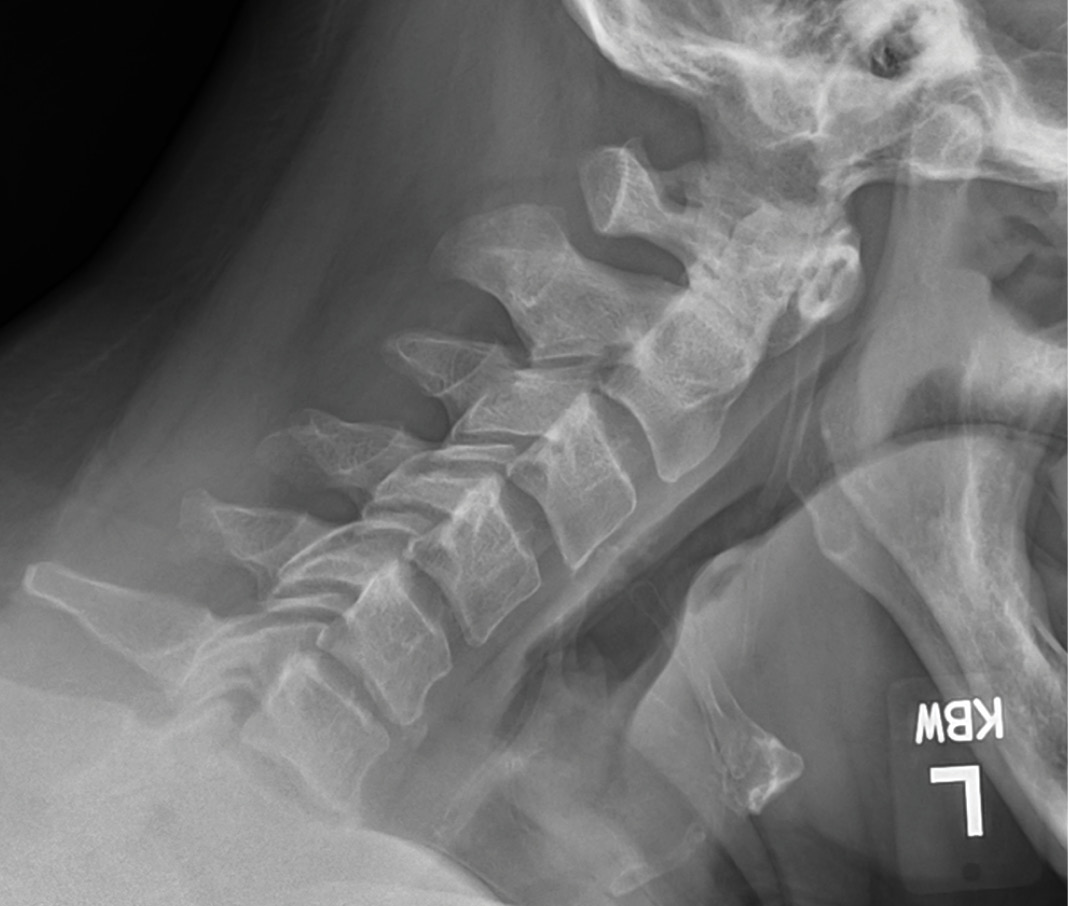

MRIs illustrated mild degenerative disc disease from C4-6 with disc herniations at both C4-5 and C5-6. The axial slice through C4-5 showed a right central disc herniation causing central and mainly right-sided foraminal stenosis. The axial slice through C5-6 showed a central disc herniation also causing central and mainly right-sided foraminal stenosis. The axial slice through C6-7 showed a left-sided disc herniation causing some left-sided foraminal stenosis, however, the patient did not demonstrate any left-sided symptoms.

Upon examination, the patient had good motion on flexion-extension, so fusion was not considered at all. My operative plan was to use prodisc cervical devices and replace both discs at C4-5 and C5-6, giving me the flexibility to use either a domed or flat implant.